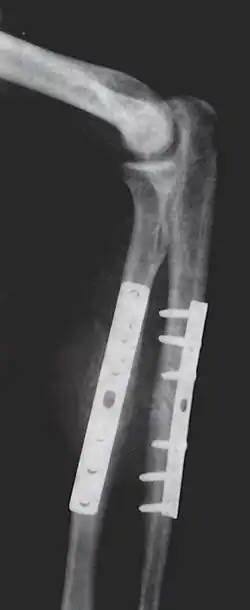

Metallic implants to repair fractures to the radius and ulna, note the visible break in the ulna (right forearm)

Internal fixation is an operation in orthopedics that involves the surgical implementation of implants for the purpose of repairing a bone, a concept that dates to the mid-nineteenth century and was made applicable for routine treatment in the mid-twentieth century.[1] An internal fixator may be made of stainless steel, titanium alloy,[2] or cobalt-chrome alloy.[3]